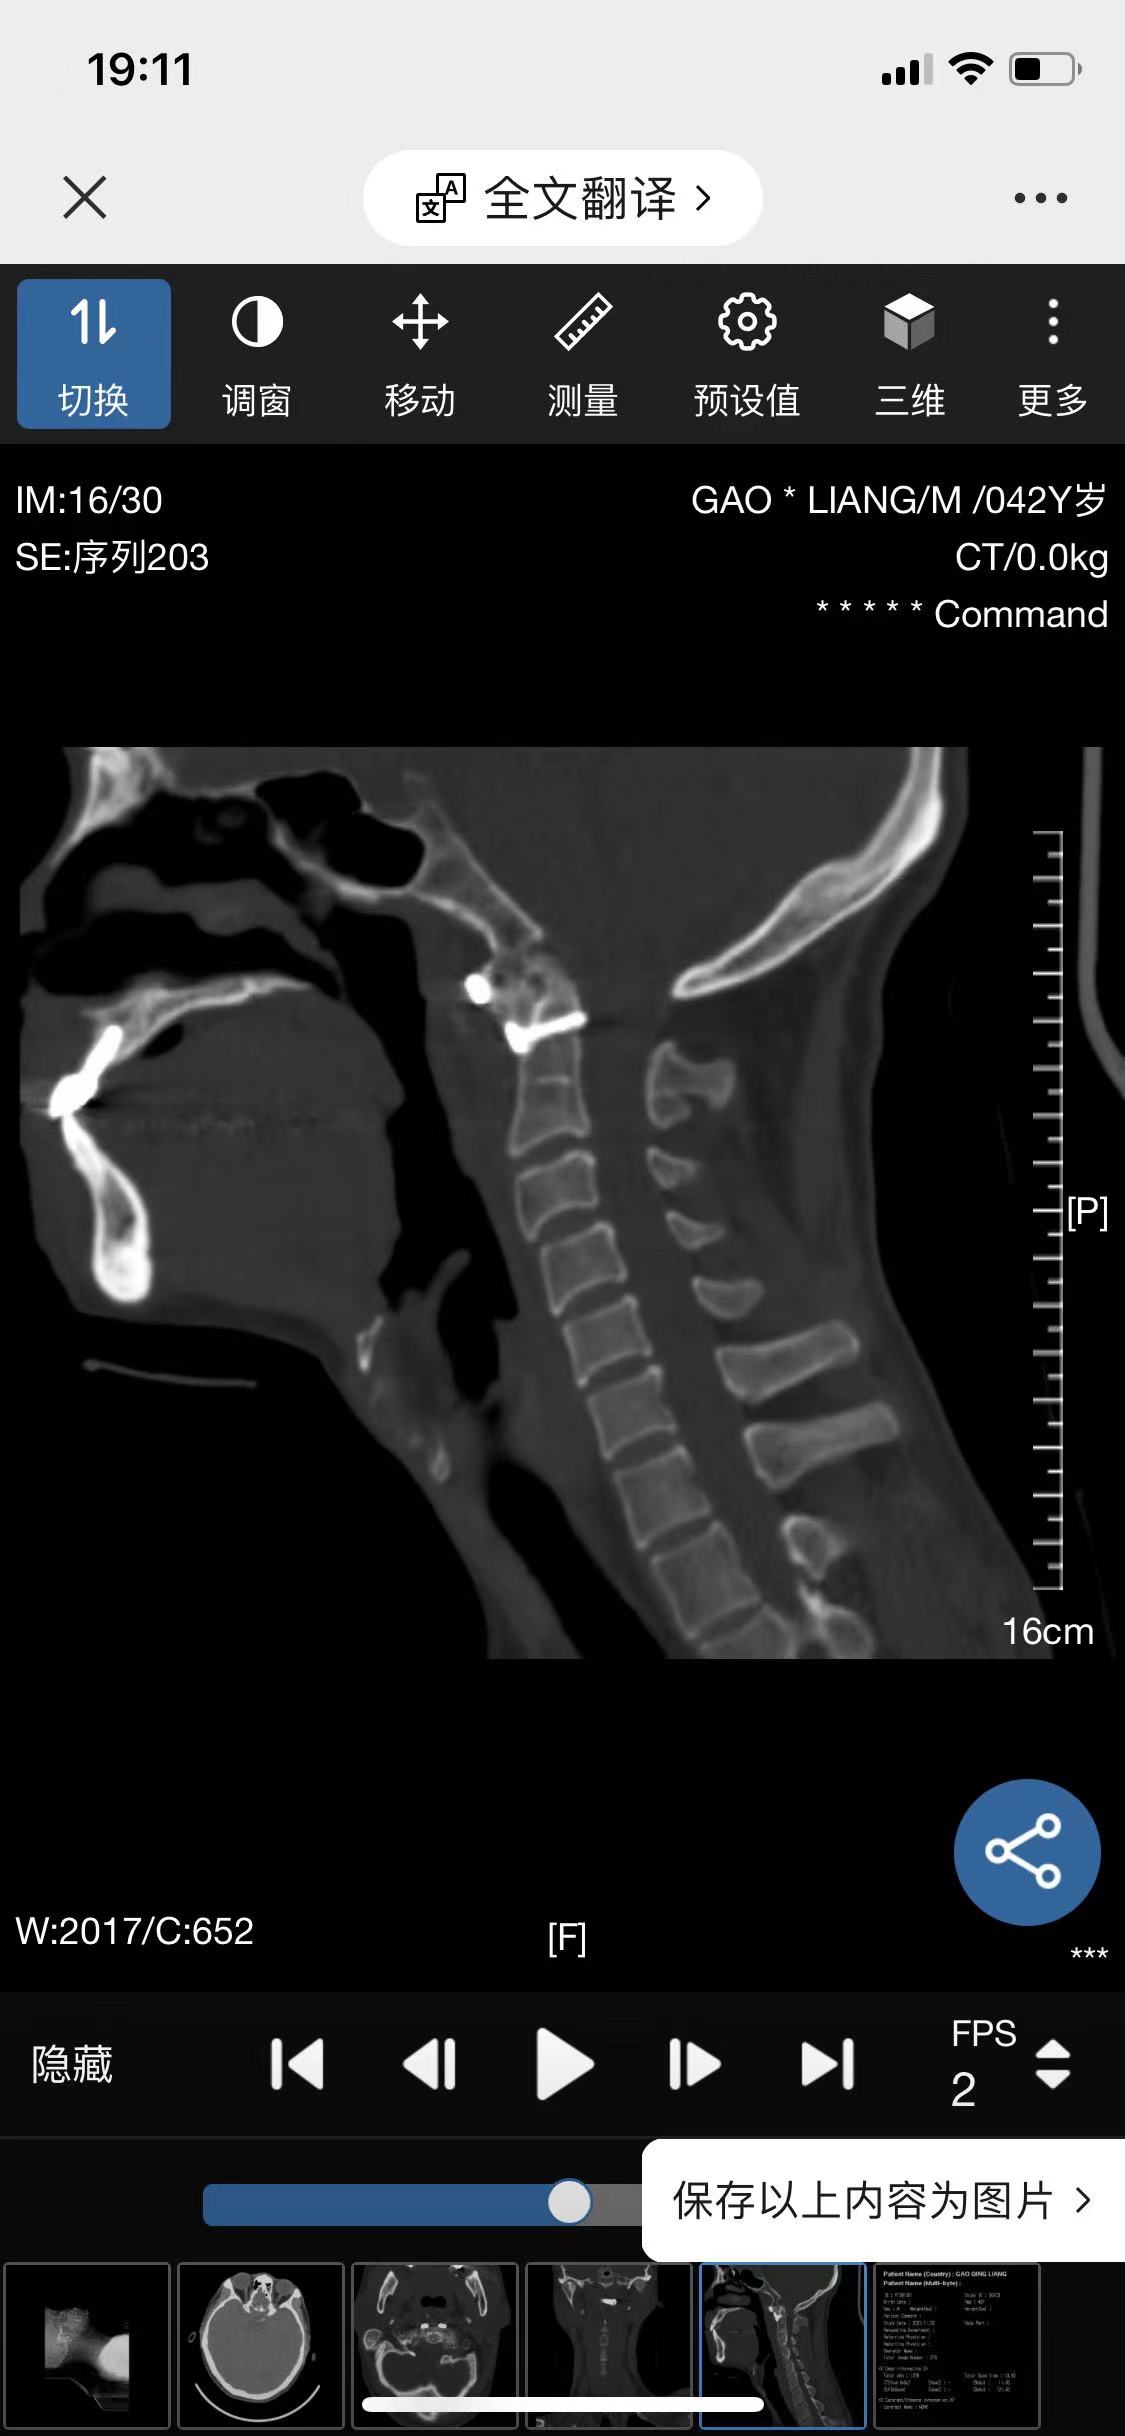

• 诊断:寰枢椎脱位

• 影像:

• 术后影像: